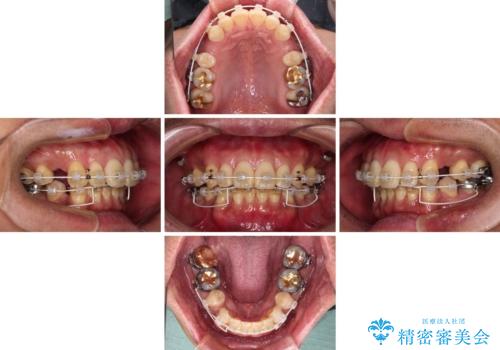

- 審美装置

- 治療期間

- 2年

非常に咬合力が強いため、抜歯したスペースが閉じるのか不安でしたが、順調に歯が移動し、予定よりも早く治療を終えることができました。